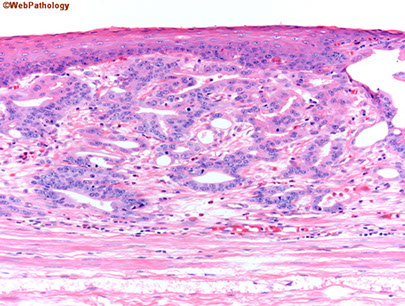

Micro: classic changes are basal cell hyperplasia (reactive change, >1/5 thickness of epithelium), elongation of vascular papillae (>2/3 of epithelial thickness), and intraepithelial eos and lymphs; usually not prominent inflam (except in severe cases)

mixed acute and chronic inflammatory cells in the epithelium and lamina propria along with reactive epithelial changes. Note basal and supra-basal cell hyperplasia and elongation of the lamina propria papillae. Inflammation is seen both within the epithelium and in the lamina propria.

GERD histology

An important histologic feature of reflux esophagitis is the elongation of lamina propria papillae to reach as high as the top 1/3 of the squamous epithelial thickness. Focal surface erosion is also seen at the left upper corner.